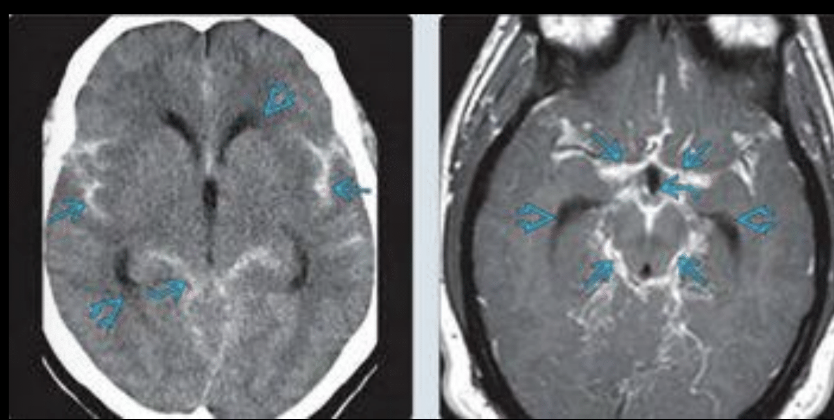

Comunicante o extraventricular

Obstrucción del flujo LCE a cisternas basales o HSA (causa más común)